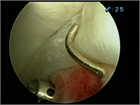

1. 単純X線撮影と読影のポイントを追加し、大腿骨寛骨臼インピンジメント(FAI)の疫学・関節症性変化への進行に関する最新の文献を参考に加筆した。